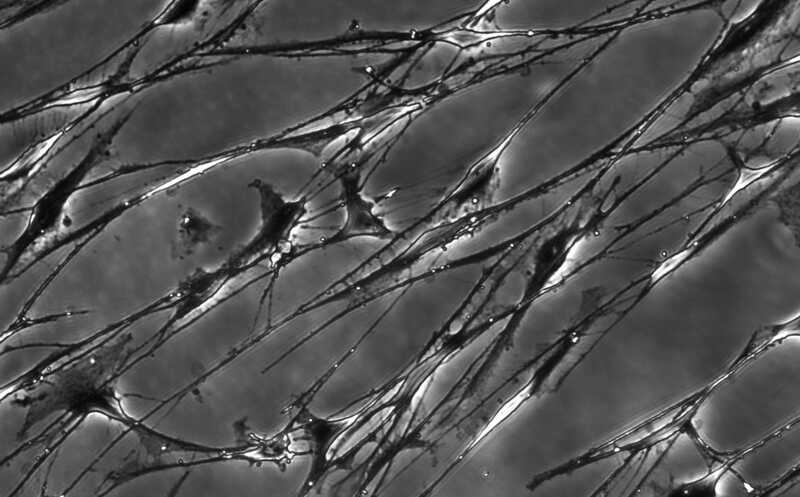

Шванновские клетки (основной тип глии) в культуре

Credit:

123rf.com